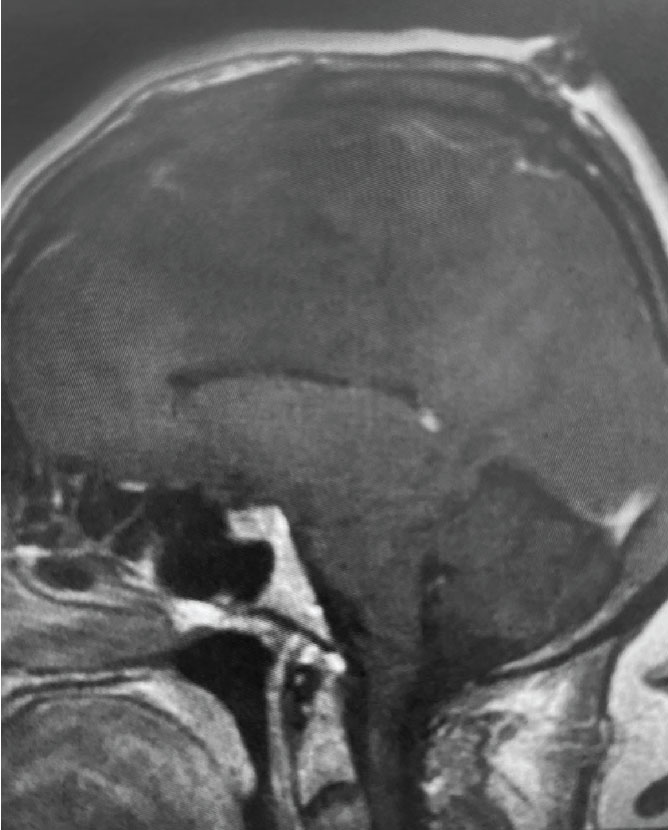

Fig 2. A) Post-operative, post-contrast, sagittal MRI.

Treatment: Given the size and location of this tumor, the best treatment was surgical removal. Surgery was performed by Dr. Michael Brisman. A craniotomy exposed the tumor along the convexity as well as the superior sagittal sinus. The tumor was removed, as was the involved convexity dura and the affected segment of the sagittal sinus. Removed dura and skull were replaced with duraplasty (with artificial dura) and a titanium mesh cranioplasty.

Outcome: The patient did very well and made a full recovery.